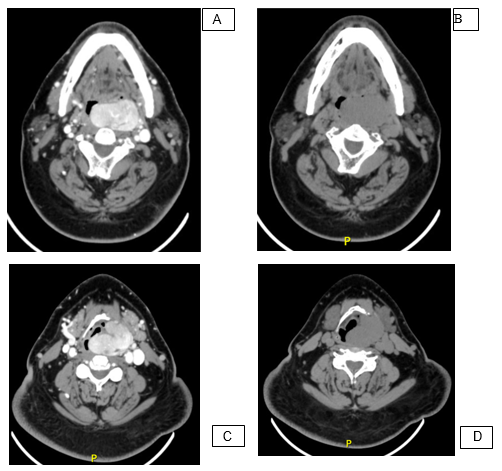

CT and MRI scans revealed a solid left parapharyngeal lesion, hyper vascular and well defined that enhances with contrast, of 6.1 x 3.8 x 5.1 cm in volume (Figure 1). Biopsy reported a SFT, without necrosis and a low mitotic index, positive for STAT-6, S-100, desmin and vimentine. A cervical approach with mandibulotomy was performed posterior to endovascular embolization of the facial artery, which was the main vascular supply. A complete tumor resection was achieved. The mandible was reconstructed with titanium plates and a tracheostomy was performed for airway protection (Figure 2). The patient had a favorable recovery with no complications and being able to eat normally. The definitive biopsy confirmed the diagnosis. At one-year follow-up the patient showed no recurrencies.

Figure 1 CT showing the tumor at a mandible level (A and B) and Hyoid bone level (C and D) It is remarkable how it changes with contrast imaging.